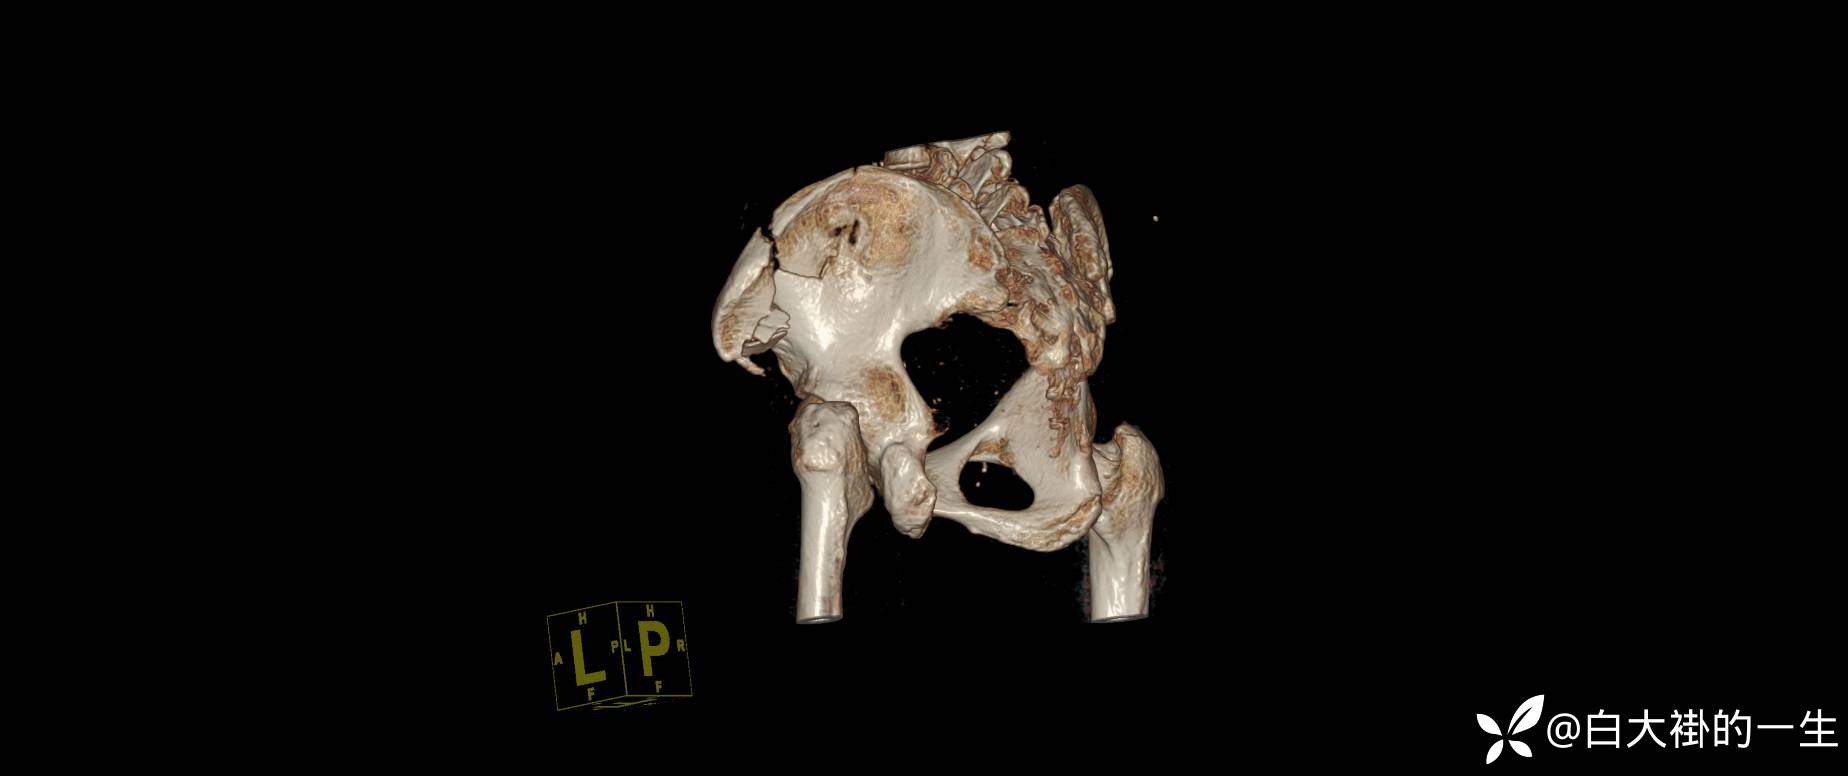

2024-08-03外院DR:左髂骨粉碎性骨折。

入院诊断:1.左髂骨粉碎性骨折;2.左髋部皮肤擦伤。

影像学如图: